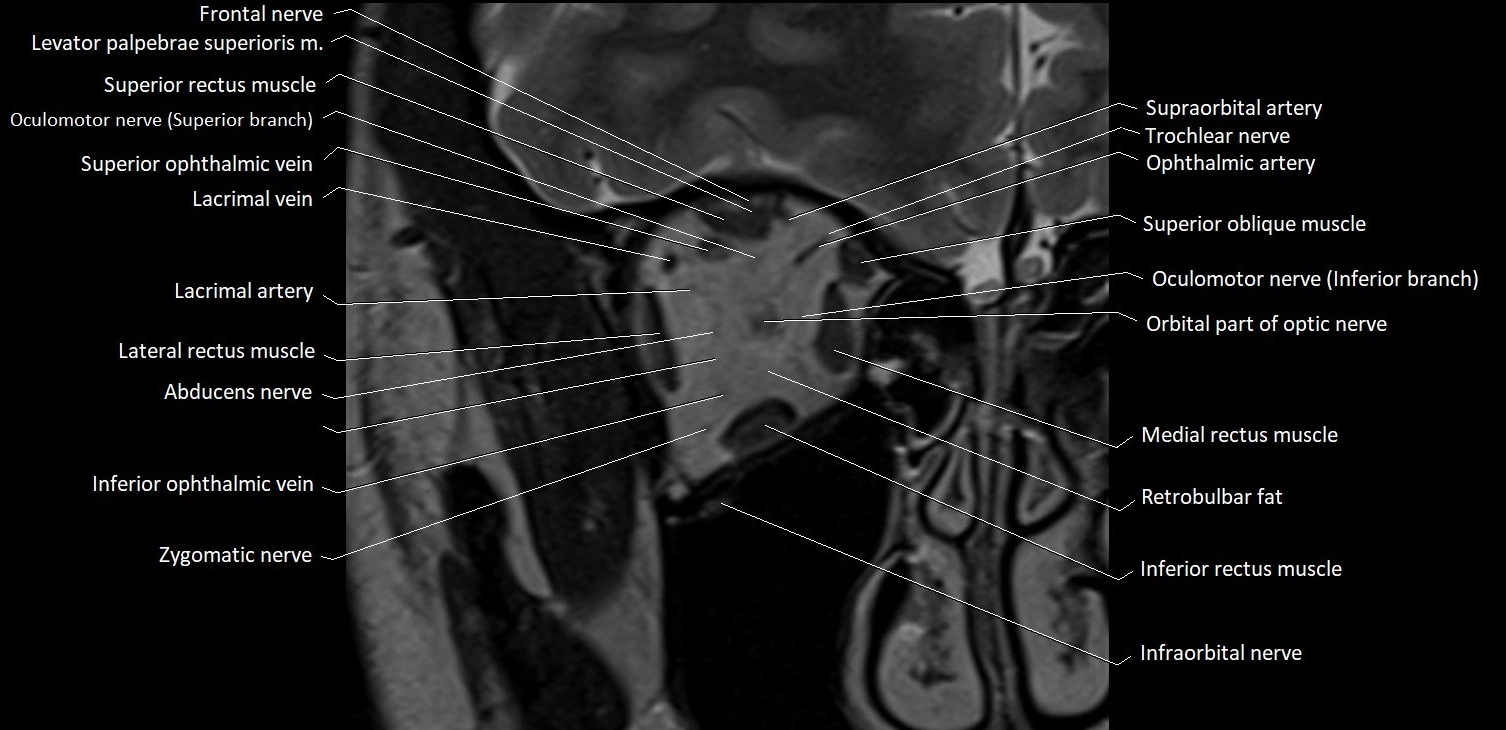

- Abducens nerve (Cranial nerve VI)

- Abducens nerve (orbital part )

MRI images